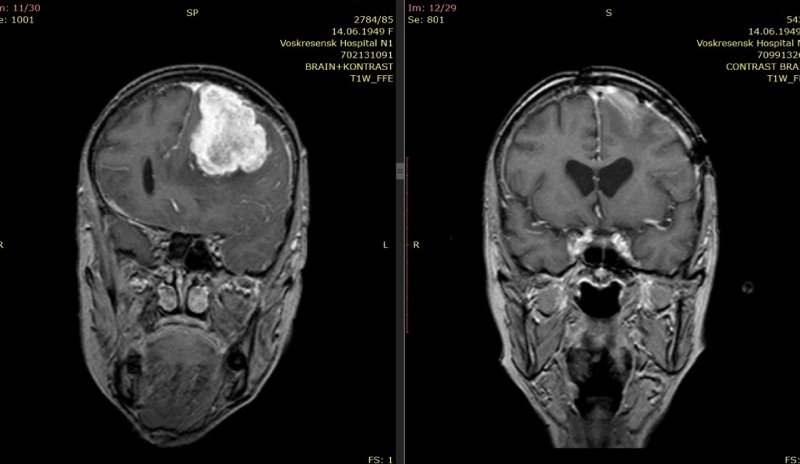

МРТ головного мозга до и после операции